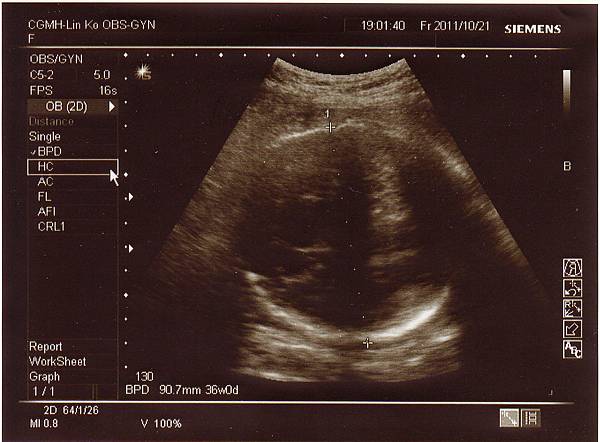

一開始產檢時,醫生量了頭圍結果約38週,也就是大了一周左右,

後來又換了角度量小了一些,但仍是正常範圍,